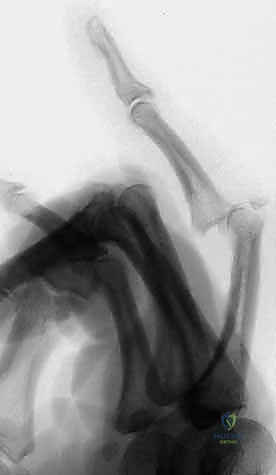

كيف يمكننا تثبيت كسر مفتت إلى قطع صغيرة جداً، وفي نفس الوقت نسمح للمريض بثني وفرد إصبعه في اليوم التالي للعملية؟ الإجابة العبقرية تكمن في "التثبيت الخارجي الديناميكي".

ما هو التثبيت الخارجي الديناميكي؟

هو نظام جراحي يعتمد على إدخال أسلاك معدنية دقيقة (K-wires) في العظام السليمة فوق وتحت مكان الكسر. يتم توصيل هذه الأسلاك خارج الجلد بهيكل خارجي (إطار - Frame) يحتوي على نظام مطاطي أو نوابض. هذا الإطار مصمم هندسياً ليسمح بحركة المفصل في محور واحد فقط (الثني والفرد)، مع منع أي حركة جانبية أو انزلاق ظهري.

مبدأ "الشد الأربطي" (Ligamentotaxis)

هذا هو السر السحري وراء نجاح التقنية. بدلاً من محاولة فتح المفصل جراحياً وتثبيت القطع العظمية الصغيرة جداً بمسامير (وهو أمر قد يدمر التروية الدموية للقطع العظمية ويؤدي إلى نخرها)، يعتمد التثبيت الديناميكي على تطبيق قوة شد مستمرة (Traction) عبر المفصل.

هذا الشد يؤدي إلى شد الكبسولة المفصلية والأربطة المتصلة بالقطع العظمية المكسورة. قوة الشد هذه تجبر القطع العظمية المفتتة على العودة إلى مكانها التشريحي الصحيح والاصطفاف بشكل سليم حول السطح المفصلي، وكأننا نقوم بتجميع قطع "البازل" دون لمسها مباشرة!